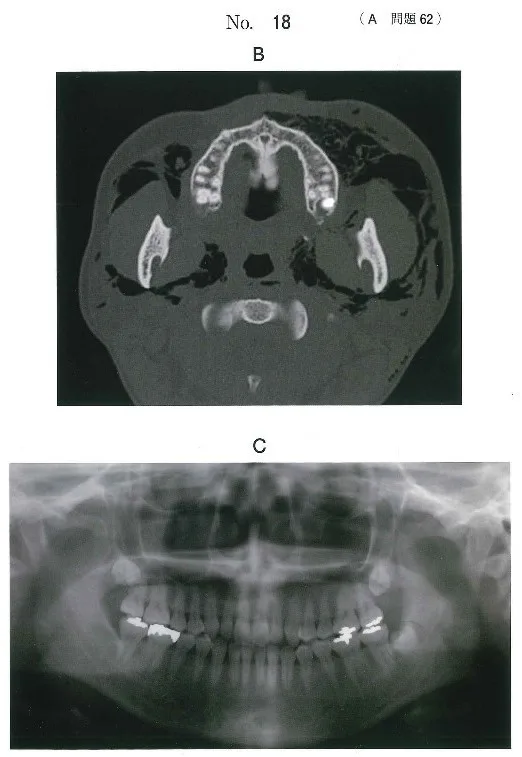

40歳の女性。左側頰部の腫脹を主訴として来院した。

30分前にかかりつけ歯科医で下顎左側埋伏智歯の抜去直後から腫脹が出現したため、紹介された。

初診時の顔貌写真(別冊No.18A)、CT(別冊No.18B)及び抜歯前のエックス線画像(別冊 No.18C)を別に示す。

適切な対応はどれか。2つ選べ。